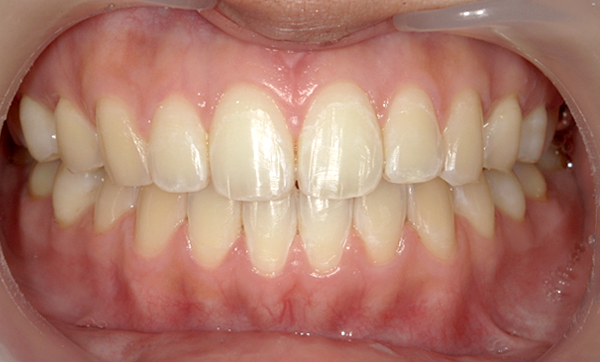

症例_008 「上下の前歯」症例

治療期間:13ヶ月金額:57万円+税40代女性捻転歯前歯のガタガタ

Before | After |

症例_008

治療リスク:後戻りの可能性